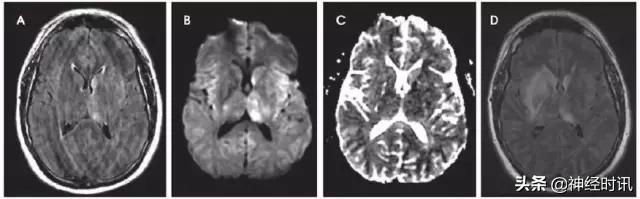

克雅氏病(CJD)是由于朊蛋白错误折叠导致的快速进展性、传染性、致死性神经退行性疾病。DWI比FLAIR或T2WI更加敏感,并伴ADC降低。CJD患者有对称性基底节受累和对称性或非对称性皮层受累(图10)。

图10 一例48岁女性,精神状态改变、亚急性记忆减退伴步态异常1年,近期出现人格改变。MRI显示双侧基底节、丘脑、皮质弥散受限(A:DWI,B:ADC)和T2-FLAIR(C)高信号。患者被诊断为CJD。